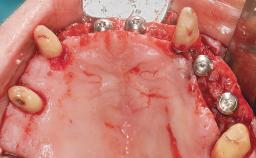

A 35-year-old Caucasian female presenting with advanced periodontal disease involving both the maxillary and the mandibular dentition was referred for evaluation. The patient, a non-smoker in good general health, requested treatment for recurrent periodontal abscesses, tooth mobility, and discomfort during chewing, as well as restoration of her missing teeth with a fixed prosthesis to improve mastication and esthetics. All residual maxillary teeth exhibited plaque deposits, deep pockets, bleeding on probing, and class III mobility and were evaluated as hopeless. All residual mandibular teeth except tooth 37 could be maintained after periodontal therapy.

| Bone Augmentation | Horizontal|Staged|Vertical |

| Augmentation Materials | Autogenous block(s) |